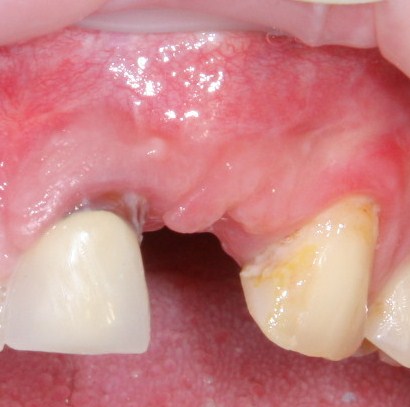

Реставрация фронтальной группы зубов.

Имплантация — Станислав Васильев       Протезирование — Давид Ахинян

Признаюсь, с такими клиническими ситуациями мы сталкиваемся нечасто. Хотя бы потому, что утрата зубов в области улыбки существенно снижает уровень социализации, и люди, способные «забить» на восстановление боковых жевательных зубов, изо всех сил стараются сохранить зубы передние в более-менее приемлемом виде.

Некоторое время назад мы подсчитали, что из 1000 установленных имплантатов всего 152 (немногим более 15%) используются для опоры протезов в эстетически значимой зоне:

А немедленное протезирование ( т. е., фиксация протеза или коронки на только что установленный имплантат) удаётся еще реже, несмотря на очевидные преимущества, хотя бы потому, что для его реализации необходимы следующие условия:

— идеальное позиционирование имплантата

— крутящий момент не менее 15 Нсм